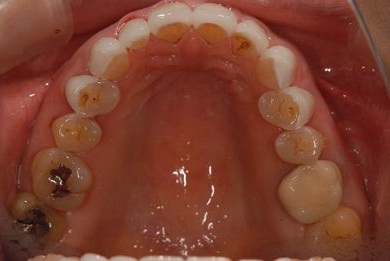

部分矯正治療+セラミック治療

| 性別/年齢 | 女性 / 54歳 | ||||||||||||||||||||||||||||||||

| 主訴 | 下の前歯のゆがみが気になり、相談。 | ||||||||||||||||||||||||||||||||

| 治療方針 | 上顎前歯の叢生を部分矯正にて審美的回復を行い、上顎前歯はラミネートベニアにて審美的回復を行う。 | ||||||||||||||||||||||||||||||||

| 治療内容 | 唇側部分矯正(ホワイト)、オールセラミックラミネートベニア8本 | ||||||||||||||||||||||||||||||||